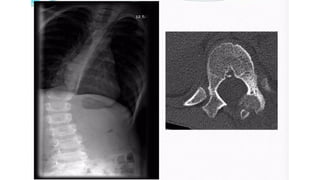

• L o c a t i o n

• • Long bones 50-60%, typically metaphysis, Lower>Upper limb

• • Spines and sacrum = 20-30%

• • Craniofacial - jaw, basisphenoid and pns

Plain film features

• An expansile lytic lesion

• S i z e = 2 - 2 0 c m

• Z o n e o f transition - can be ill-defined

• Thin sclerotic margin

• • Cortical breach and soft tissue extension

• CT & MRI

• • To delineate soft tissue extension

• • Shows characteristic fluid-fluid levels (representing areas of

• blood of variable ages)

• ***Other benign lesions with fluid-fluid levels

• • G C T

• • Chondroblastoma

Differentials of ABC in spines - Osteoid osteoma and Osteoblastoma